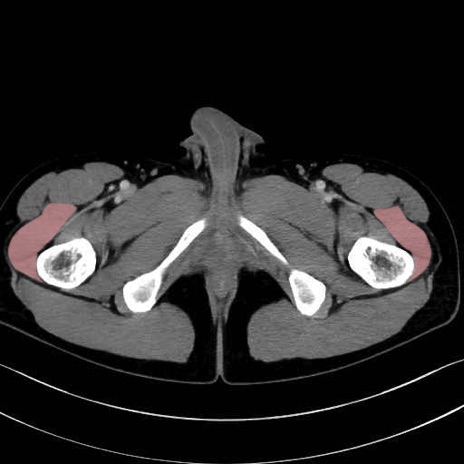

外側広筋 (Vastus lateralis)